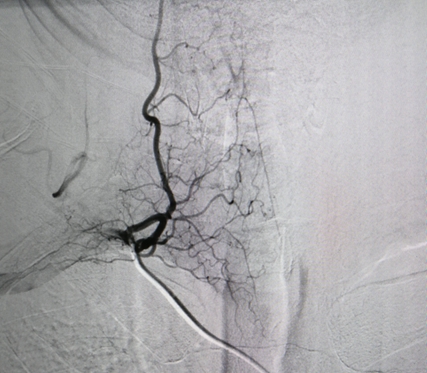

右侧甲状颈干造影清晰显示颈部脊髓动脉

12月20日,在放射介入科主任胡康新教授指导下,汤金成和李毅副主任医师为患者实施手术。手术在最新型“介入手术机器人”——Artis zeego血管造影机下进行。因设备先进,医师技艺娴熟,手术进展顺利,在一个多小时内,经股动脉穿刺分别一一选择性插管到双侧颈动脉、椎动脉,双侧锁骨下动脉、甲状颈干及胸廓内动脉,双侧第1-12肋间动脉等20多支血管内造影。造影清晰地显示了脑及脊髓的全部供血血管,成功排除了动静脉血管畸形等血管性疾病的可能性。